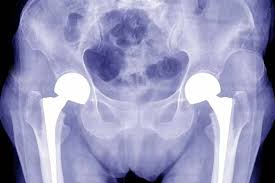

Hip joint problems can slowly erode mobility and comfort. When pain, stiffness, and limited movement disrupt life, timely surgical care becomes essential. Fortunately, CGHS hip replacement in Rewa is now accessible through Varunam Super Speciality Hospital, with expert orthopedic care by Dr. Utsav Agrawal. Under the Central Government Health Scheme (CGHS), eligible beneficiaries from Rewa and nearby regions can receive cashless hip replacement surgery without upfront financial burden. As a result, patients experience relief from chronic pain, improved mobility, and enhanced quality of life. Varunam Super Speciality Hospital stands out for its advanced infrastructure, modern surgical techniques, and patient‑centered services. Consequently, individuals covered under CGHS can undergo safe, effective hip replacement without worry.

CGHS hip replacement refers to hip joint surgery provided under the Central Government Health Scheme. This government initiative allows eligible beneficiaries to access medical treatment without paying at the time of service. At Varunam Super Speciality Hospital, eligible patients receive comprehensive hip replacement care, including pre‑operative assessment, surgery, hospital stay, post‑operative rehabilitation, and follow‑up. Dr. Utsav Agrawal leads the orthopedic team, ensuring that every surgical decision focuses on precision, safety, and long‑term function.

CGHS hip replacement at Varunam Super Speciality Hospital treats a range of hip conditions that deteriorate joint health and mobility. These include advanced osteoarthritis, avascular necrosis (AVN), injury‑related joint damage, and degeneration due to long‑term wear. Patients often report chronic pain, difficulty walking, and stiffness that disrupt everyday life. Without timely care, these conditions can worsen, leading to muscle weakness and reduced quality of life.

The CGHS hip replacement process at Varunam Super Speciality Hospital begins with a detailed pre‑operative assessment. Dr. Utsav Agrawal reviews clinical history, physical examination findings, and imaging results like X‑rays and MRI scans. Based on this evaluation, he creates a customized surgical plan that accounts for age, activity level, and overall health.

During the procedure, precise techniques and high‑quality implants help restore the hip joint’s natural function. The surgical team ensures patient comfort and safety throughout the operation. After surgery, patients receive structured post‑operative care that includes pain management, wound care, and guided physiotherapy.